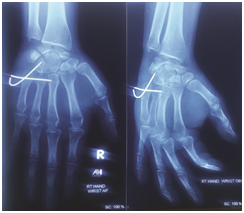

Initially treatment started with NSAID and hand elevation. On the next day hand swelling was minimally subsided, closed reduction and percutaneous k-wire fixation was done under general anaesthesia with c-arm guidance. The reduced base of fifth metacarpal bone fixed to fourth and partly third metacarpal base by passing a k-wire transiously which maintain the inter metacarpal joint. Another k-wire passing obliquely through base of fifth metacarpal to hamate, it give stability of hamato-metacarpal joint.

Per-operative radiographs ensure the base of fifth metacarpal placed in position. Clinically there was no depression on dorsomedial aspect of proximal position of Right carpus and little finger deformity was corrected. All finger joints moves freely. Proper dressing of k-wire entering points done. Finally apply cock-up slab for immobilization of wrist joint and metacarpal bones. Post-operative x-ray ensure the base of fifth metacarpal and both k-wires in position.

Figure 2 Postoperative Radiographic view of AP and Oblique.